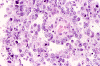

A survey at low-magnification shows a necrotic neoplasm (Panel F). The tumor cells arrange in different patterns. The tumor cells are densely packed in some areas but loosely packed in other areas.  At medium-magnification, several different patterns of architecture are disclosed. The most commonly encountered pattern in this case is a reticular-microcystic arrangement of cells (Panel G). In a significant amount of other areas, there are hypocellular to myxoid non-neoplastic stroma lined by a single layer of neoplastic cells (Panel H, I). The tumor cells have moderate to large nuclei with substantial pleomorphism. The chromatin is clumpy and hyperchromatic (Panel J). In some areas the tumor cells has an hepatoid appearance featured by a smaller nuclei with substantial amount of amphophilic cytoplasm (Panel K). Schiller-Duval bodies are occasionally noted (Panel L). A variable number of eosinophilic globules are also present and they are strongly positive for periodic acid-schiff (PAS) reaction (Panel M). Results of immunohistochemistry are as follows:

Yolk sac tumor arising in the thymus often have extensive invasion into the adjacent tissue. In this cases, the tumor is still confined. The histology is quite typical for a yolk-sac (endodermal sinus) tumor. The reticular-microcystic pattern being illustrated here is the most common pattern being encountered.  Only a small number of Schiller-Duval bodies are present. The large cells with hepatoid look correspond to the hepatoid pattern in yolk sac tumor. The solidly arranged sheets of tumor raise the possibility of an embryonal carcinoma. However, the nuclear pleomorphism, although significant, is still short of that from embryonal carcinoma. The extracellular, PAS(+), eosinophilic hyaline globules are also typical for yolk sac tumor. These globules are often immunoreactive for a-fetal protein and a-1-antitrypsin. In our case, they are only positive for a-1-antitrypsin. The lack of CD30 immunoreactivity, again, does not support a diagnosis of embryonal carcinoma.

Yolk sac tumors exhibit a wide range of histologic patterns that differ considerably from each other. In most cases, a mixed histologic pattern is present and, not infrequently, one or two patterns may predominate. The most common pattern is the microcystic-reticular pattern. The other histologic patterns included endodermal sinus, solid, alveolar-glandular, polyvesicular vitelline, myxomatous, macrocystic, papillary, intestinal, hepatoid, and spindle cell. Although there is a rich variation in architecture, the variations in cytologic features are less impressive. The tumor cells are medium to large and have clear to pale, granular cytoplasm. Hobnail cells are not uncommon and often seen with the papillary pattern. The nuclei are large, vesicular, and contain prominent nucleoli. Yolk sac tumors are mitotically active. Necrosis and hemorrhage are common.

Yolk sac tumor often, but not always, contains bright, eosinophilic globules. These extracellular, small, round, brightly eosinophilic, hyaline, strongly PAS-positive, diastase-resistant globules or droplets are most often associated with the microcystic-reticular pattern and endodermal sinus pattern. These globules are considered to be secreted by the tumor cells and accumulate within the cytoplasm. As the amount of secretion increases, the cell become distended and ruptures, discharging its contents into the surrounding tissue. Although characteristic, these eosinophilc hyaline globules are not diagnostic of yolk sac tumor because they are also found in other malignant tumors particularly those with poor differentiation. When they are present in specimen from fine needle aspiration, as in our case, they are metachromatic and provide a good clue for diagnosis 19, 20.